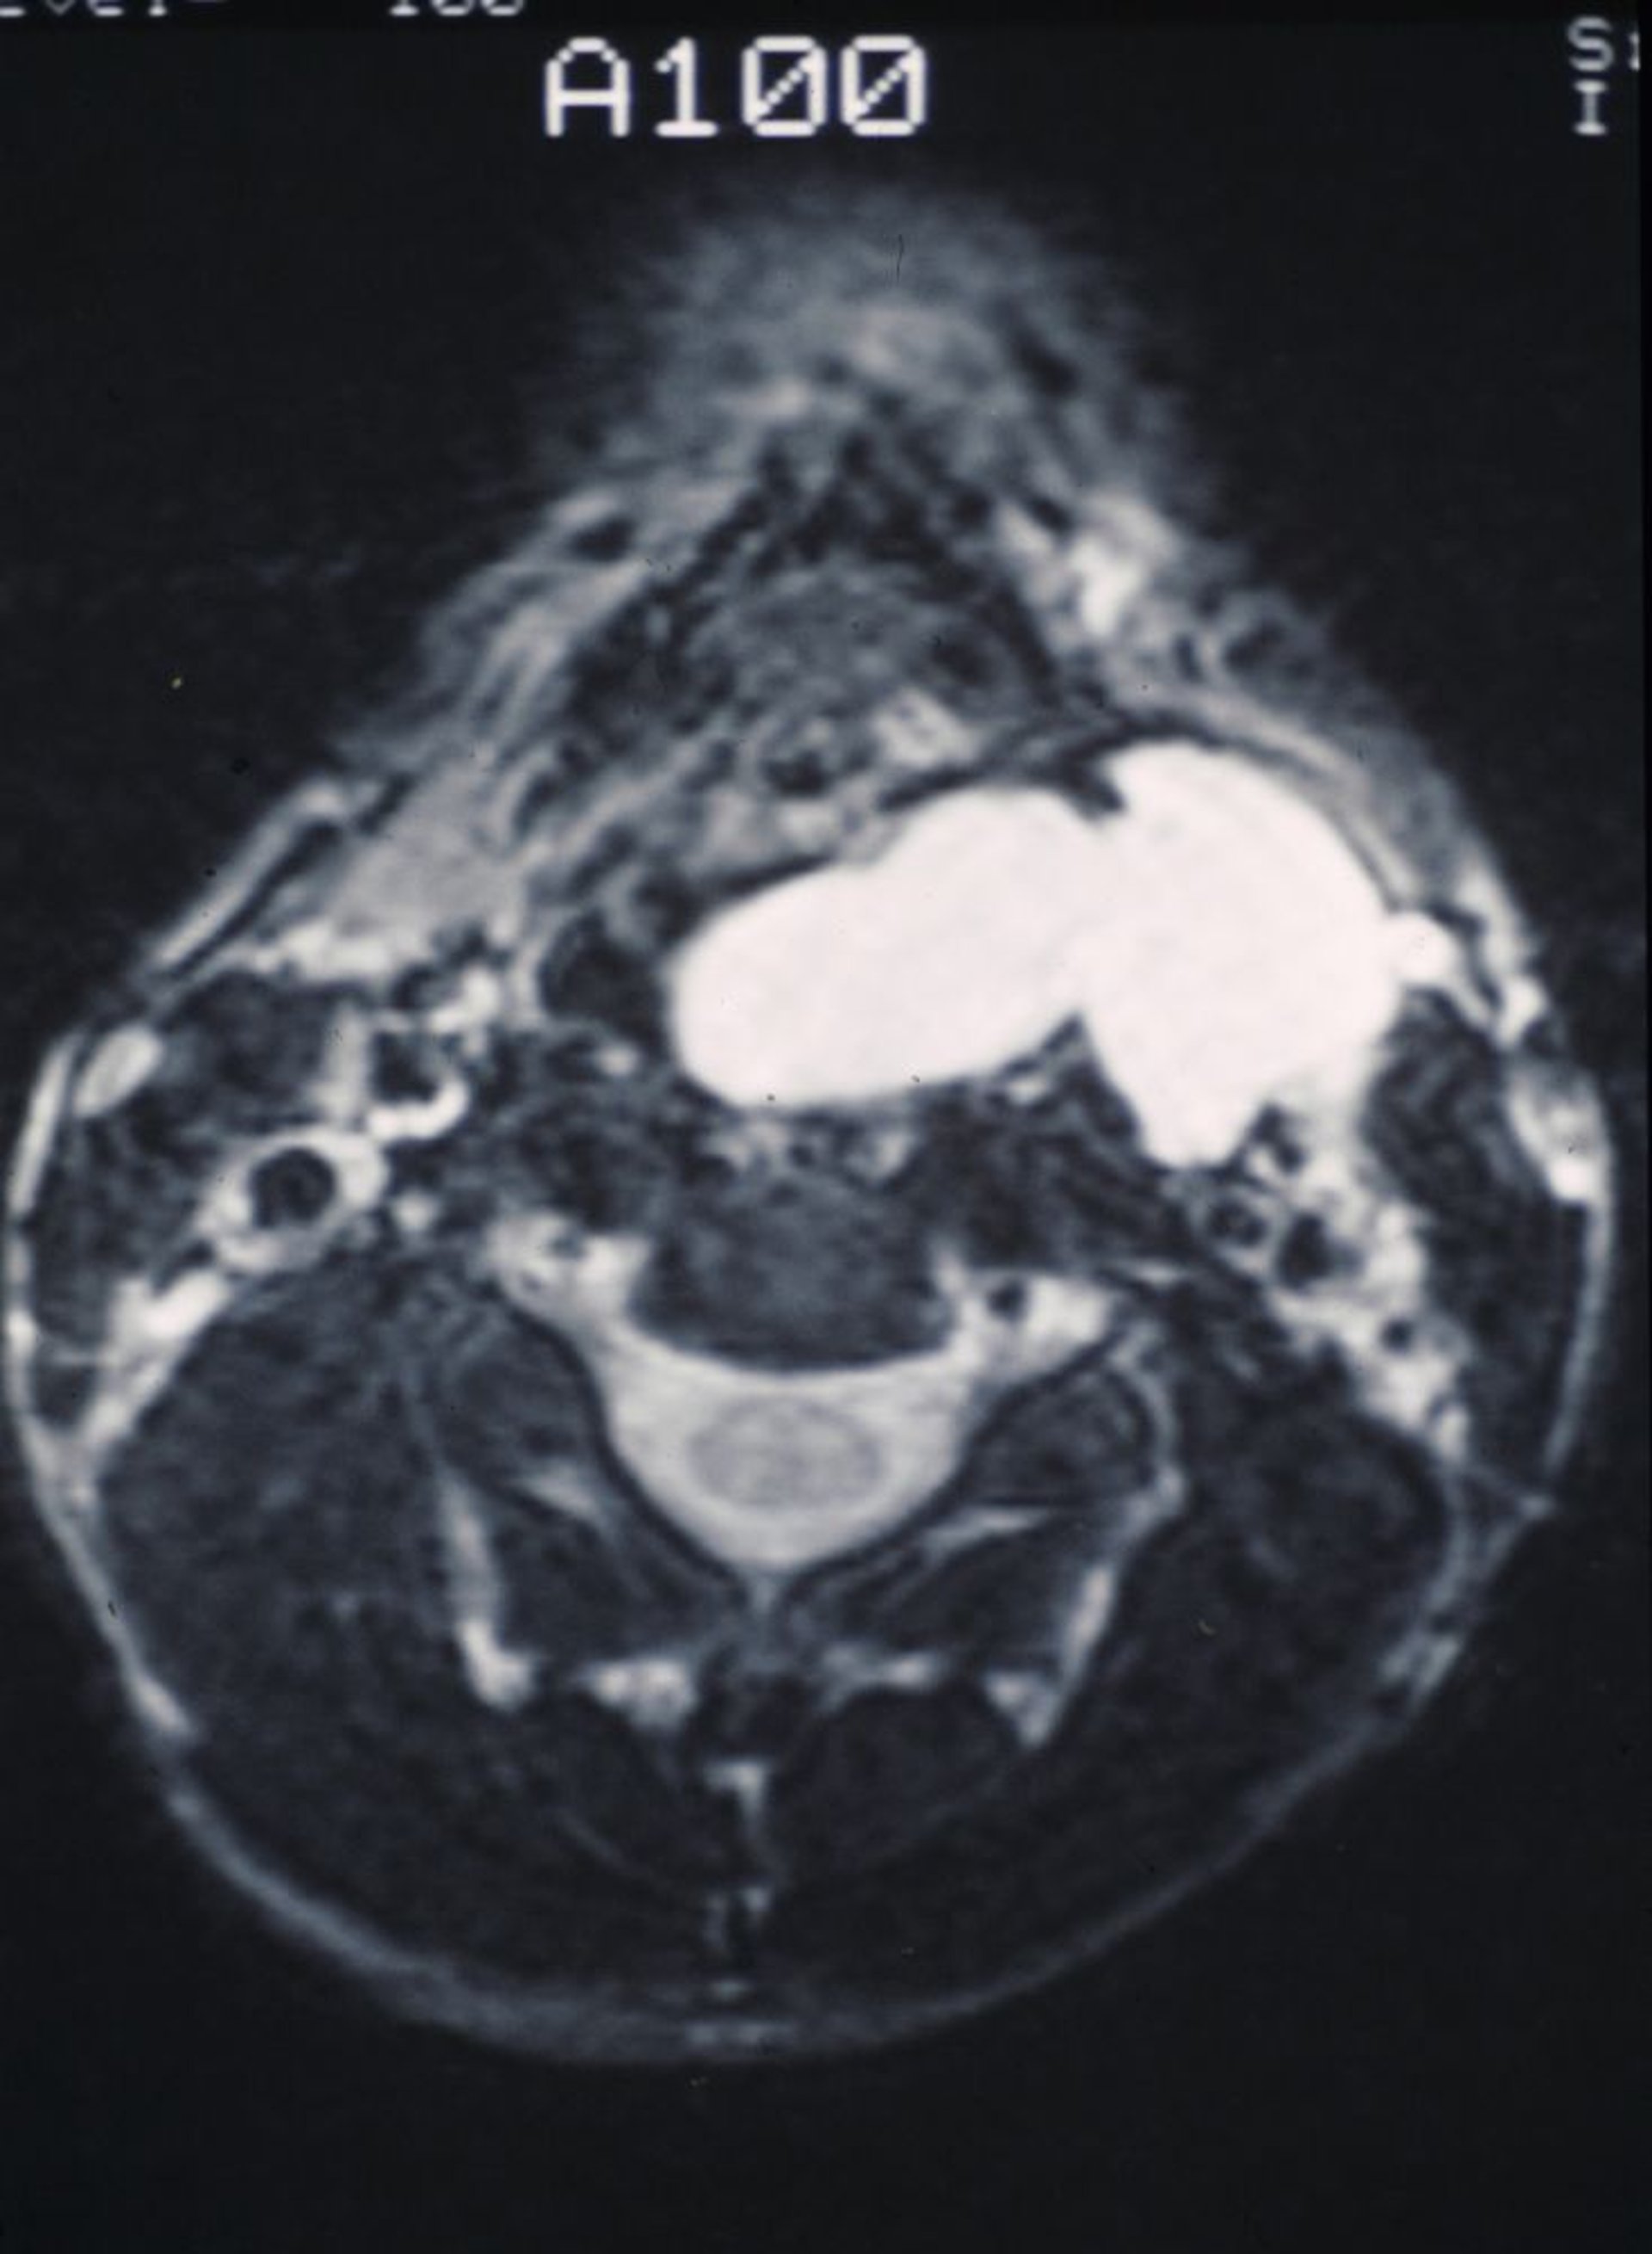

Diese CT-Aufnahme zeigt eine glatte, schleimgefüllte Laryngozele, die sich in den Rachen und nach außen in den Hals vorwölbt.

Image provided by Clarence T. Sasaki, MD.